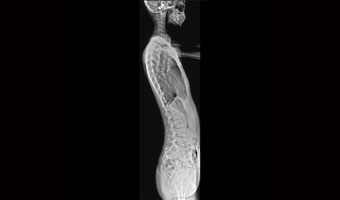

Klinik Vakalar

Tam klinik uygulama, her yerde bakım

Ortopedik yaralanmalar

Tek çekimde tam omurga ve alt ekstremite görüntüleme.

Geniş bir alanın hızlı görüntülenmesi ve lezyonun kesin lokalizasyonu için yatma pozisyonunda tam çerçeve görüntüleme.

Uygulama Görüntüleri

Acil travma